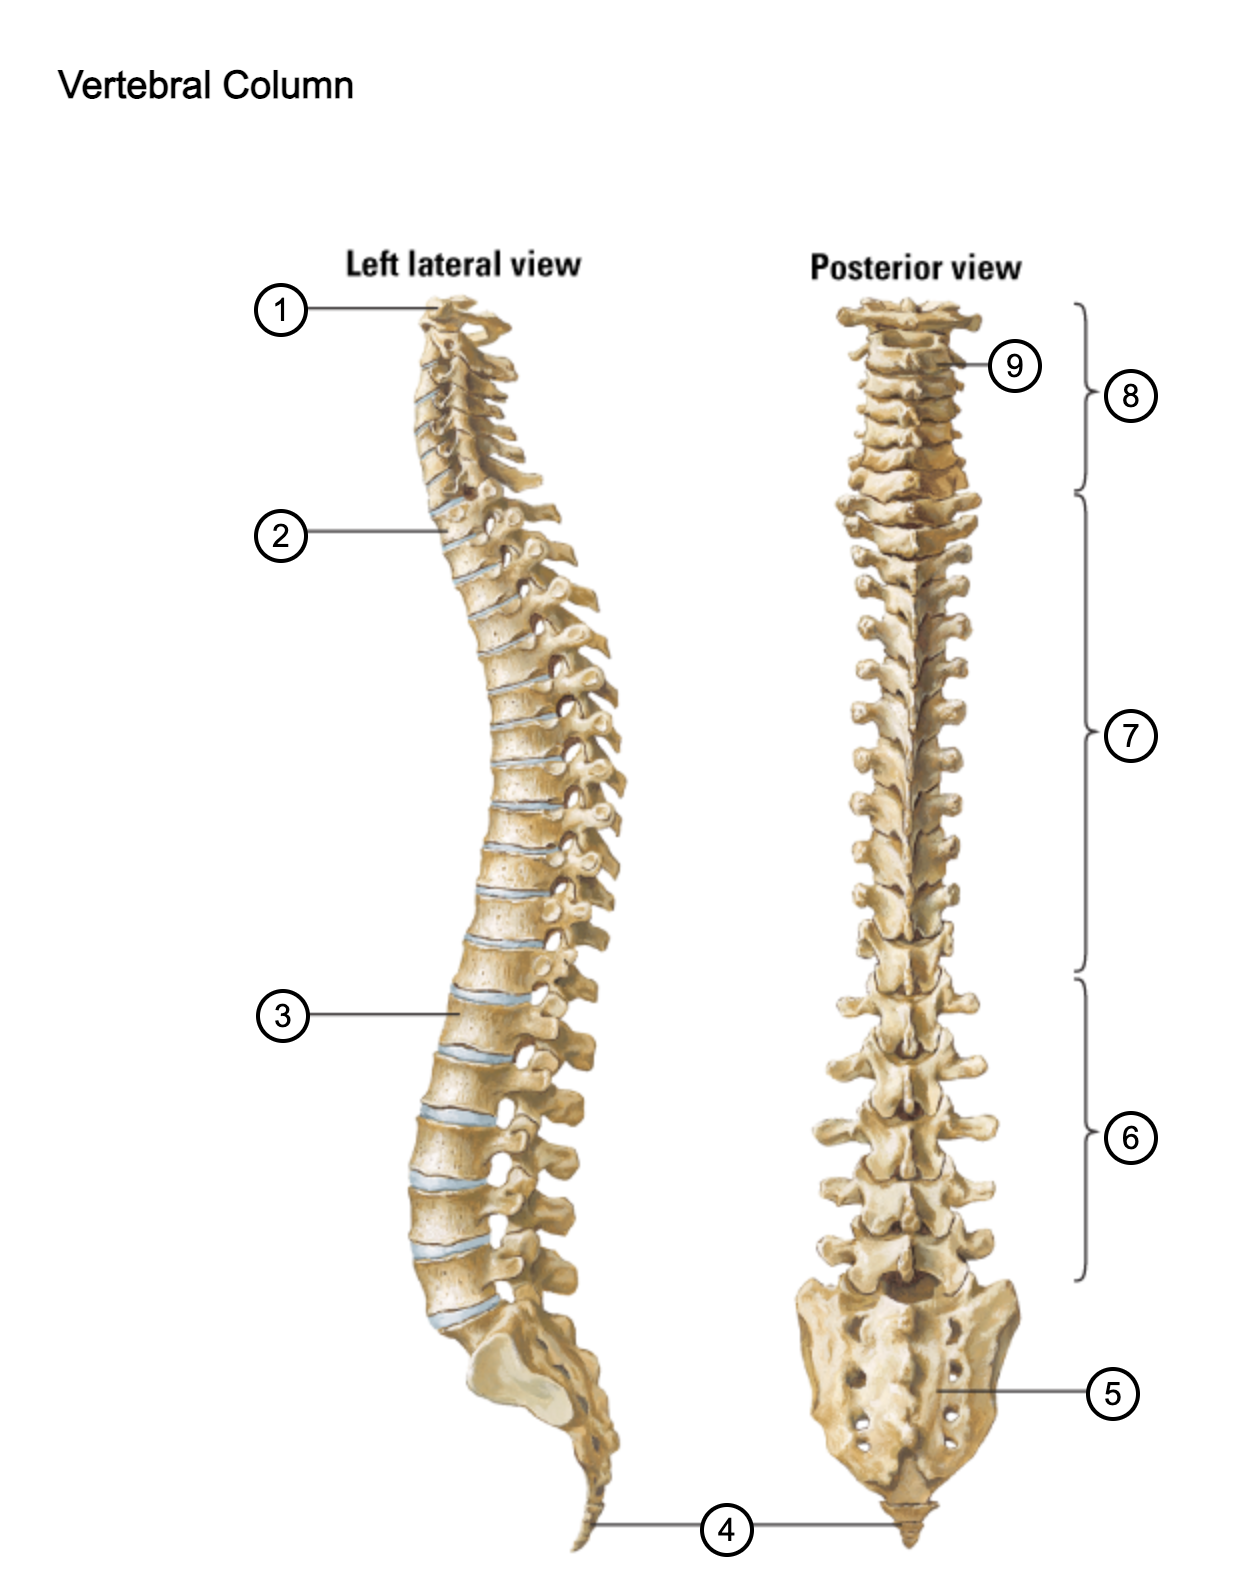

1

atlas (C1)

2

T1

3

L1

4

coccyx

5

sacrum (S1-5)

6

lumbar vertebrae

7

thoracic vertebrae

8

cervical vertebrae

9

axis (C2)